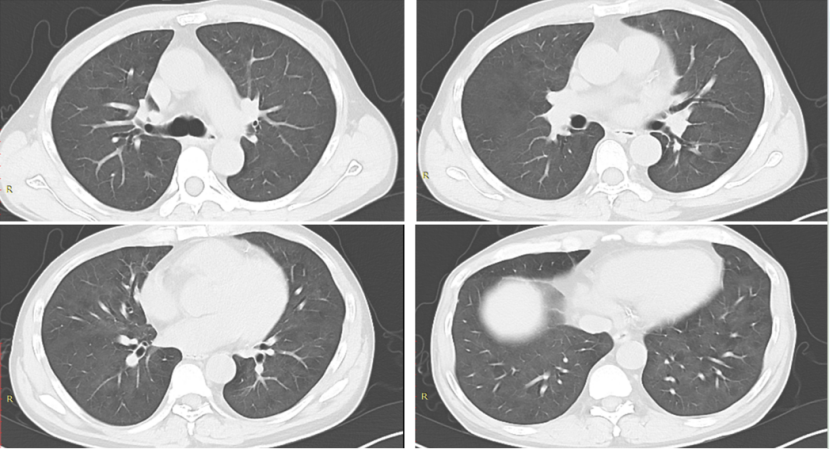

病例2:肾移植术后半年,发热3天。影像学表现并不严重(图10)。入院后完善NGS,耶氏肺孢子菌序列数330000。入院后即予SMZ+卡泊芬净+甲泼尼龙治疗,但病情仍然加重,入院10天转ICU,影像学持续进展(图11)。患者入ICU后NGS结果回报耶氏肺孢子菌序列数843433周后死亡。

图片

10  患者入院胸部CT

11  患者病程中胸部CT变化情况

文献报道,SMZ可以结合二氢叶酸合成酶(DHPS)基因位点从而抑制DHPS的合成TMP可以结合二氢叶酸还原酶(DHFR)基因位点从而抑制DHFR的合成达到杀灭耶氏肺孢子菌的作用国外学者1998年即发现了耶氏肺孢子菌DHPS基因突变,且接受磺胺及氨苯砜预防患者突率远高于未预防患者(70.6%:16.6%);Van Hal等发现DHPS基因型密码子55和57突变与疾病严重程度相关,与野生型相比,患者有创通气的比例更高,且临床结局更差。这一案例提醒我们,对于SMZ治疗效果不佳的患者,应及时进行BALF二次送检,若耶氏肺孢子菌丰度值依然较高,需警惕磺胺耐药的发生,及时更换治疗方案